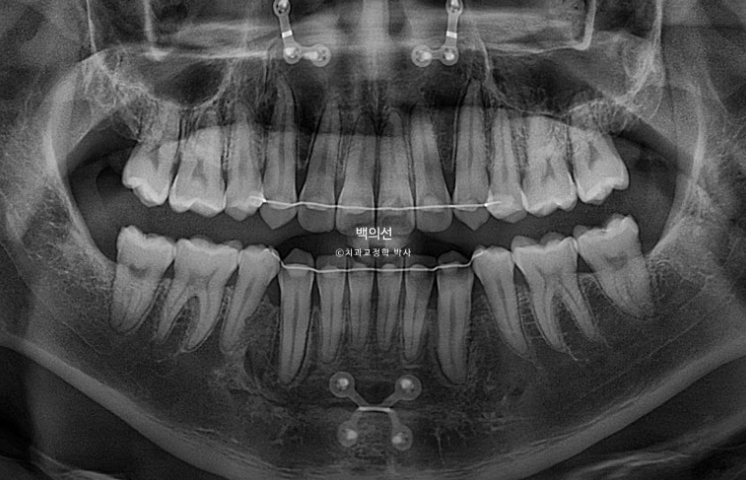

치근흡수는 없으며 치근평행도는 좋습니다.

총 치료기간은 10개월, 재제작 1회 입니다.